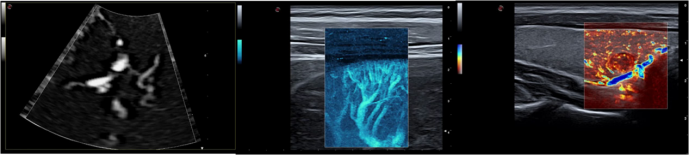

微血管“珊瑚”成像 (MicroV):

采用百胜专利计算方式,在有效保证帧频的前提下,去除背景噪声,降低周边 强回声结构信息干扰,保证清晰可视细小血管和低速血流。具有 5 种成像方式,可 应用于各类探头的不同临床应用。对于无创、快速的检测极低速血流成像有明显帮助, 可应用于:小血管、风湿、脑血管疾病诊断

猫动脉

小白鼠颈动脉

小白鼠眼睛

小黑鼠睾丸